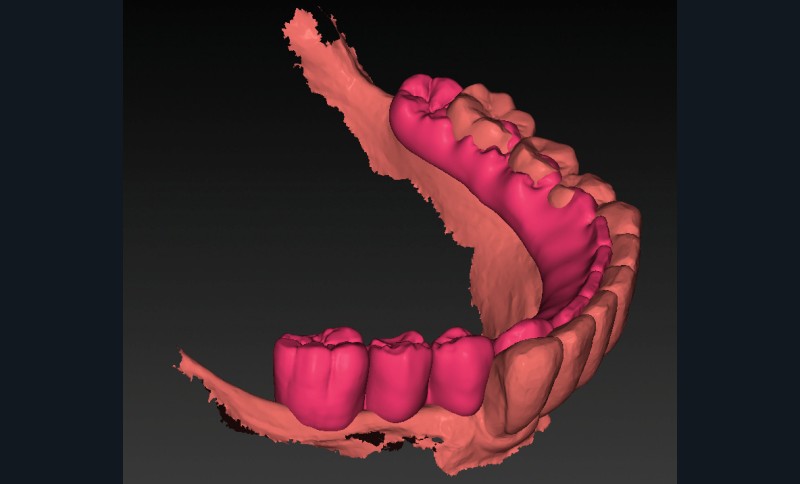

- les empreintes (fig. 3) transmises au laboratoire pour la réalisation d’un wax-up digital (fig. 4) préfigurant la position idéale des dents prothétiques. Ce modèle prothétique virtuel permet de déterminer la position, l’axe et la profondeur idéale des implants en fonction du couloir osseux, des tissus mous et du positionnement souhaité des puits de vissage.